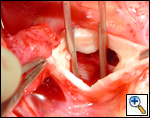

The operative approach is through a median sternotomy with the use of cardiopulmonary bypass and bicaval venous cannulation. The first dose of cold blood cardioplegia is antegrade; the remaining doses are retrograde.

High ascending aortic cannulation adjacent to the innominate artery for maximum exposure of the ascending aorta and to allow length for positioning of the patch in the ascending aorta.

One dose of antegrade cardioplegia followed by retrograde cardioplegia.

Pulmonary homograft or pericardial patches (tanned in glutaraldehyde) for the “shields”. These patches should not be too large – this will lead to aortic insufficiency.

First coronary sinus incision in noncoronary sinus to facilitate exposure of the incisions into the coronary orifice sinuses.

In most cases, the right coronary artery sinus should be opened to the left of the coronary orifice and the left coronary artery sinus to the right of the coronary orifice. Occasionally one may not have enough room between a coronary orifice and the aortic valve; in this case the incision site should be tailored to the situation.

Ensure similar orifice sizes between the proximal and distal ascending aorta after patch augmentation by the use of a sizing dilator.

Transesophageal echocardiography to assess completeness of repair, coronary blood flow postoperatively, wall motion abnormalities, and adequacy of aortic valve.